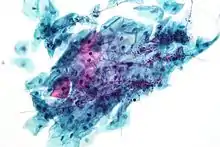

Candida

Candida species cause infections in individuals with deficient immune systems. Candida species tend to be the culprit of most fungal infections and can cause both systemic and superficial infection.[6] Th1-type cell-mediated immunity (CMI) is required for clearance of a fungal infection. Candida albicans is a kind of diploid yeast that commonly occurs among the human gut microflora. C. albicans is an opportunistic pathogen in humans. Abnormal over-growth of this fungus can occur, particularly in immunocompromised individuals.[7] C. albicans has a parasexual cycle that appears to be stimulated by environmental stress.[8]

Other species of Candida may be pathogenic as well, including Candida stellatoidea, C. tropicalis, C. pseudotropicalis, C. krusei, C. parapsilosis, and C. guilliermondii.[9]